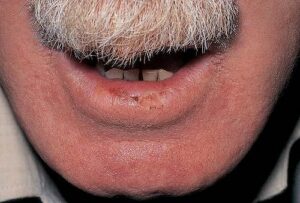

Actinic cheilitis=التهاب الشفتين الضيائي

ACTINIC CHEILITIS

Actinic cheilitis, a premalignant condition due to chronic ultraviolet light exposure, typically affects the lower lip, resulting in an ill-defined, atrophic, white, scaling plaque that may obliterate the vermillion border. Microscopically, solar elastosis, hyperkeratosis, and atypical basal keratinocytes are seen. Any ulceration or induration requires a biopsy to rule out malignant transformation